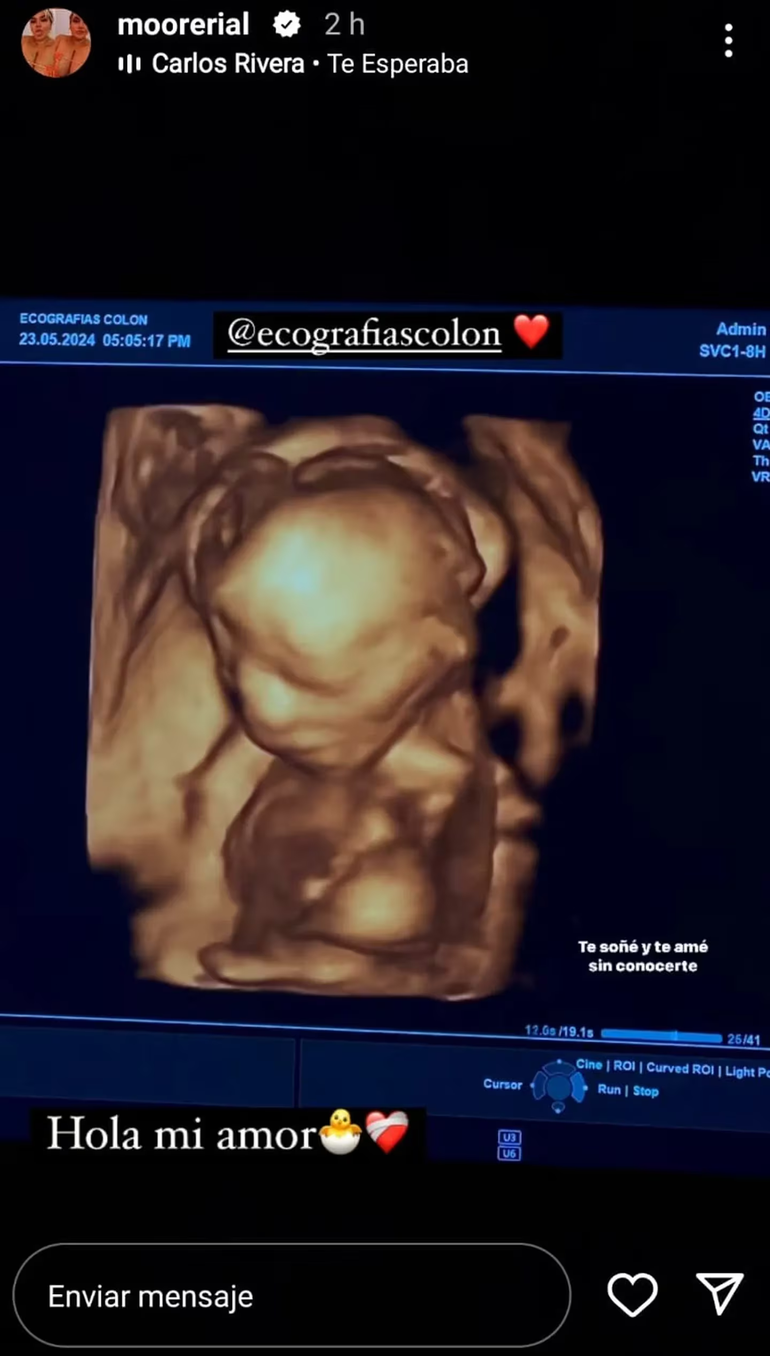

Morena Rial sorprendió a sus seguidores de Instagram con una imagen del bebé que se encuentra esperando y del que todavía no quiere decir el sexo ni el nombre. Publicó una captura de la última ecografía que le hicieron y se mostró muy feliz, ya que falta poco para tenerlo en sus brazos.

“Hola mi amor. Te soñé y amé sin conocerte”, comentó junto a la imagen posteada en la mencionada red social, donde se ven los rasgos de la criatura, fruto de su amor con un boxeador.